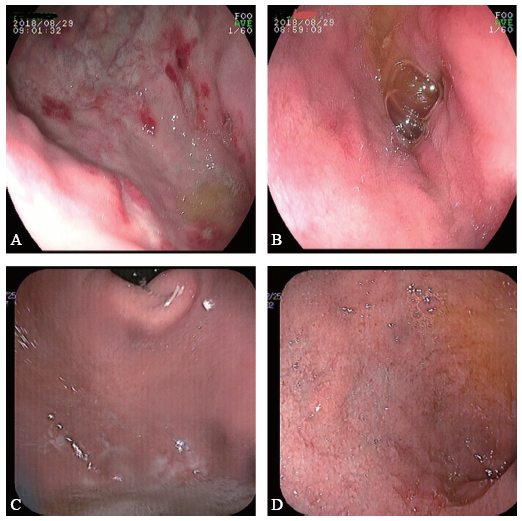

图1 一例EG患者治疗前后胃镜对比图

A、B:治疗前胃镜显示胃底、十二指肠球部多发溃疡及糜烂;C、D:治疗后胃镜显示胃底、十二指肠球部溃疡基本愈合

X线胸片提示双肺未见异常。胃镜检查显示胃底、胃体、胃窦及十二指肠仍有多发散在溃疡,直径约0.5 ~ 0.8 cm(图1A、B),病理活组织检查(活检)提示胃黏膜呈慢性活动性炎症,固有层较多嗜酸性粒细胞浸润,约60个/高倍镜视野(图2A)。结肠镜显示回肠末段、升结肠、横结肠、乙状结肠及直肠局部黏膜充血、水肿,多发散在点、片状糜烂及溃疡,直径约0.1 ~ 1.0 cm,病变间隔有正常黏膜(图3A、B)。病理活检提示肠黏膜呈慢性活动性炎症,固有层较多嗜酸性粒细胞浸润,其中回盲部约100个/高倍镜视野,结肠约60个/高倍镜视野(图2B、C)。胶囊内镜显示小肠黏膜多发散在糜烂、溃疡灶,溃疡形状不规则,直径约0.3 ~ 0.8 cm,病变呈跳跃性,病变之间有正常黏膜(图4A)。

全腹部增强CT提示肠系膜周围见多发肿大淋巴结,未见“靶征”“木梳征”等征象。综合病史、临床表现及上述检查结果,拟诊为EG,给予口服泼尼松15 mg,每日2次。1周后患者腹痛症状显著改善,复查嗜酸性粒细胞绝对值0.01×109/L,嗜酸性粒细胞百分比1.1%。患者出院后继续口服糖皮质激素维持治疗。4个月后患者复诊时腹痛症状基本缓解,复查胃镜(图1C、D)、结肠镜(图3C、D)及胶囊内镜(图4B)均显示消化道溃疡大部分愈合,溃疡数量较前明显减少,病变范围较前明显缩小。半年后随访患者已停用糖皮质激素,腹痛等症状未复发,食欲及大便情况也较前明显改善。最后诊断:EG。